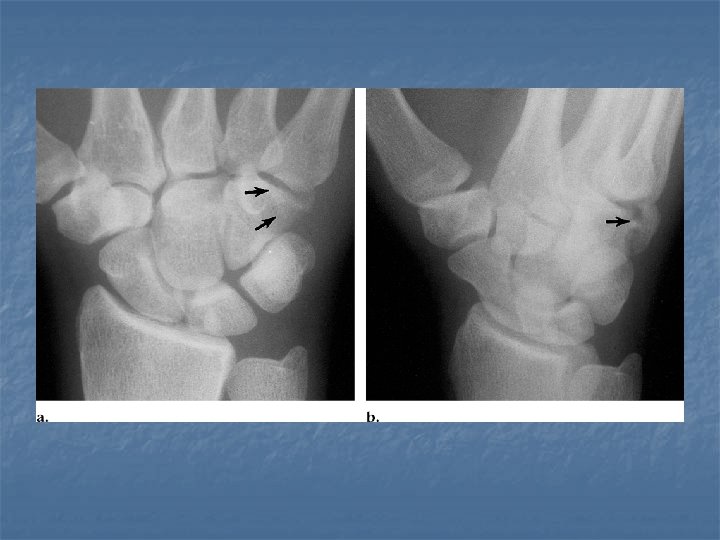

Scapholunate dissociation n n Results from injury of the scapholunate ligament Radiographicaly diagnosed by Terry Thomas sign due to widening of the space between the scaphoid and lunate more than 2 mm

Terry Thomas sign

Rotatory subluxation of scaphoid n n n Related condition to scapholunate dissocaition where there is in addition rotation of the scaphoid along its long axis Radiographically diagnosed by signet ring sign: volar tilt of the scaphoid makes it appear foreshortened with its tuberosity seen end on giving a cortical ring. Radiographs in dorsovolar view should be in the neutral position or with ulnar tilt for this sign to be reliable one

Neutral position signet ring sign Radial tilt Normal scaphoid